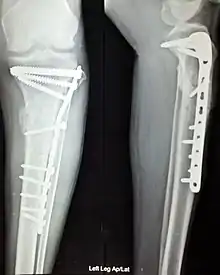

The use of intramedullary rods to treat fractures of the femur and tibia was pioneered by Gerhard Küntscher of Germany. This made a noticeable difference to the speed of recovery of injured German soldiers during World War II and led to more widespread adoption of intramedullary fixation of fractures in the rest of the world. Traction was the standard method of treating thigh bone fractures until the late 1970s, though, when the Harborview Medical Center group in Seattle popularized intramedullary fixation without opening up the fracture.

According to applications for board certification from 1999 to 2003, the top 25 most common procedures (in order) performed by orthopedic surgeons are:[22]

- Repair of femoral shaft fracture